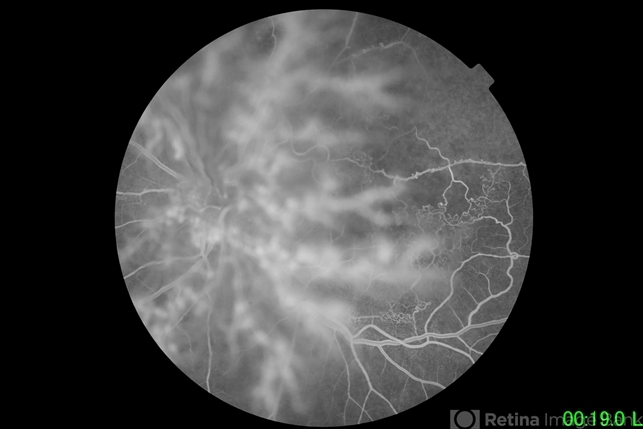

- branch retinal vein occlusion (BRVO)

- 72-year-old female with ischemic branch retinal vein occlusion. Neovascular proliferation on the posterior hyaloid. Background shows ischemic BRVO with florid neovascularization emanating from the disc.